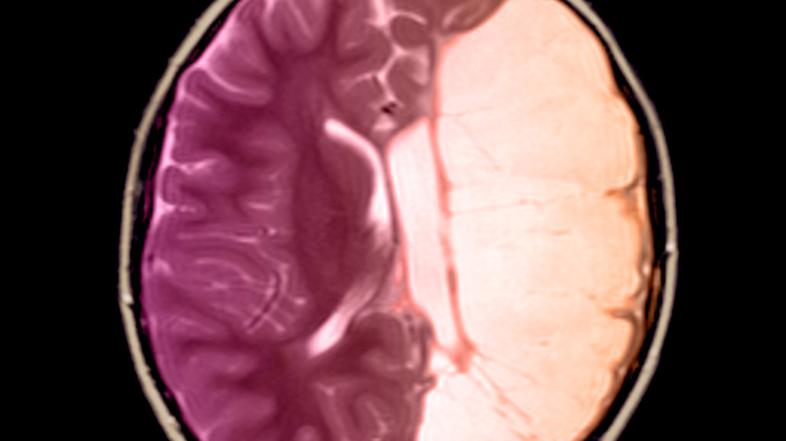

Točnih podatkov o številu oseb s cerebralno paralizo v Sloveniji ne poznamo. Po medicinskih statistikah naj bi se na 1000 otrok rodili dva do štirje otroci s cerebralno paralizo. V zvezi opozarjajo, da cerebralna paraliza ni bolezen, ampak stanje, ki ni ozdravljivo. Je posledica poškodbe razvijajočih se možganov v času nosečnosti, poroda ali v prvih dveh letih življenja.